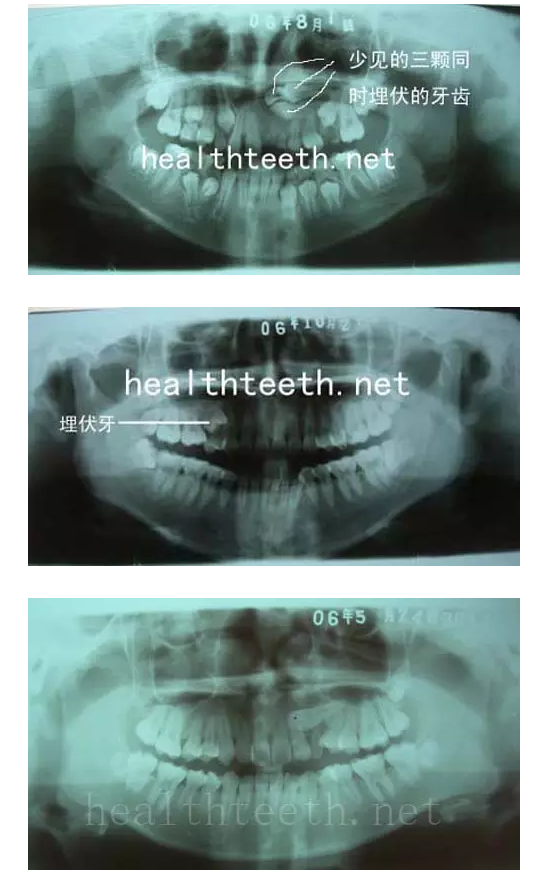

左上乳3滯留,恒3未見萌出,曲面斷層片顯示牙齒埋伏

其他埋伏牙

3、多生牙

病例1

病例2

病例3,同時多生兩顆牙齒